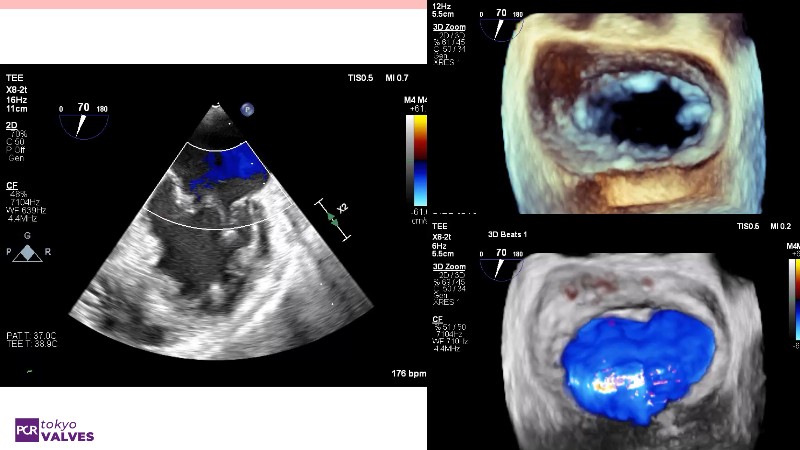

Explore the latest advancements in TEER therapy with this PCR Tokyo Valves 2025 session dedicated to MitraClip. Through expert-led case discussions, gain a deeper understanding of complex scenarios, including restricted posterior leaflet in functional mitral regurgitation, commissure lesion (A3P3), and MitraClip combined with Amulet.

This session also highlights key findings from the OCEAN study, shedding light on 1-year heart failure rehospitalisation outcomes with MitraClip. Additionally, discover how atrioventricular valve morphology impacts treatment strategies and how the four available clip sizes can be used to personalise and optimise TEER outcomes.